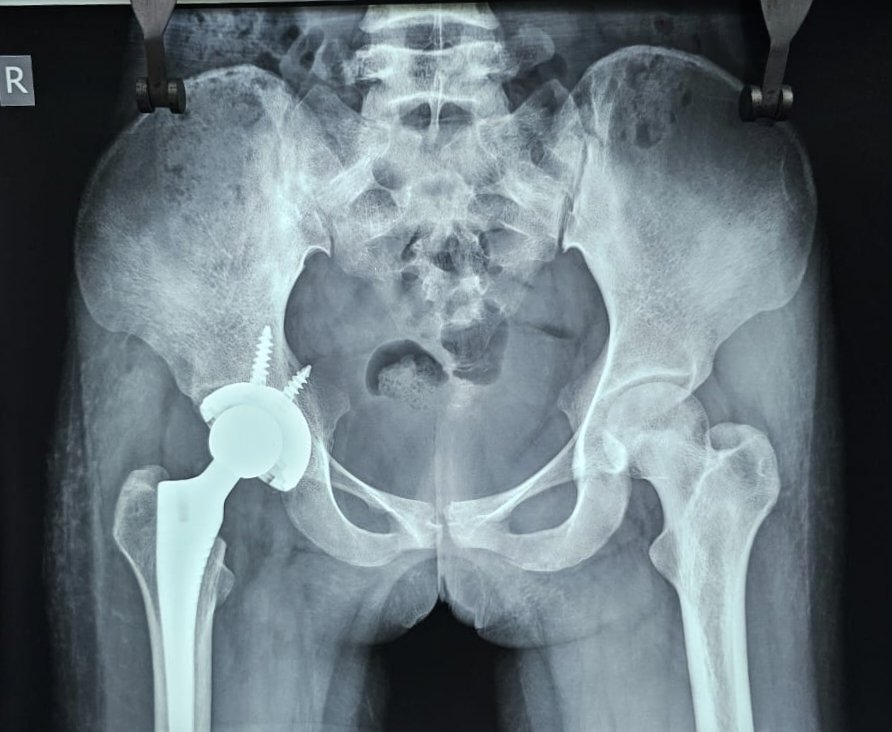

आज सिम्स के डॉक्टरों ने 21 वर्षीय 75 प्रतिशत सिकल सेल की मरीज का टोटल हिप रिप्लेसमेंट का सफल ऑपरेशन कर एक नया कीर्तिमान बनाया है।

डॉ राजीव सखूजा ने मरीज की पूर्ण जांच कराई, जिसमें उन्होंने यह पाया कि मरीज की 75 प्रतिशत रक्त कोशिकाएं सिकल सेल से प्रभावित हैं जो कि अपने आप में एक बहुत बड़ा रिस्क है। तथा सिकल सेल की वजह से उसके कूल्हे की हड्डियां पूरी तरह खराब हो चुकी है। मरीज के पिता अपनी बेटी के नियमित तकलीफ को देखते हुए यह जोखिम उठाने को भी तैयार हो गए।

इसके बाद मरीज का पूर्ण रूप से निश्चेतना एवं मेडिकल फिटनेस परीक्षण कराया गया । जिसके बाद मरीज का टोटल हिप रिप्लेसमेंट का सफल ऑपरेशन डॉ राजीव सखूजा एवं उनकी टीम ने किया। मरीज अब पूर्णत स्वस्थ है दर्द रहित है एवं बिना सहारे के चल पा रही है । यह ऑपरेशन पूर्ण रूप से आयुष्मान भारत योजना के अंतर्गत निशुल्क हुआ।